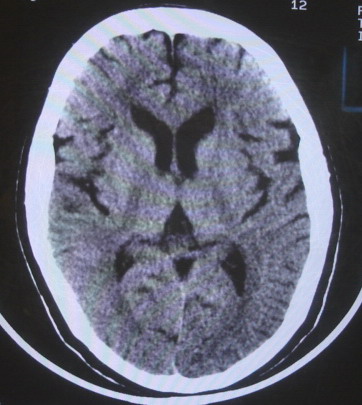

女  67岁 双下肢无力,行动不灵便

老年脑

脑萎缩,腔隙性脑梗塞.

双侧额桥束及左侧脑室旁多发腔梗塞+老年性脑改变

多发腔梗、老年性脑改变、脑白质异常。